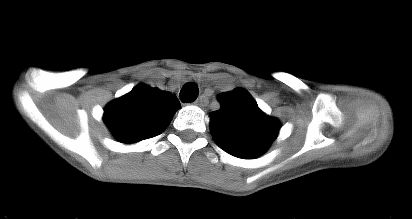

标题: CT22395:左侧肱骨头占位性病灶。 [打印本页]

标题: CT22395:左侧肱骨头占位性病灶。

这是一个17岁的花季少女,在上学期间,自觉左侧肩部不适,家人误以为是外伤引起,没有重视,近日疼痛加剧,来院就诊,ct检查发现如下.

诊断依据:1、骨质破坏,软组织肿胀。2、从纵隔窗上看,这么年轻就有纵隔淋巴结钙化,提示有可能有肺结核病史,这是诊断左肩关节结核的又一重大证据,建议结合病史并提供肺窗。

鉴别诊断:成软骨细胞瘤(位于骨骺内,囊状破坏,一般不会有软组织肿胀)

肩胛盂边缘未累及,楼主并没有上传肺窗片,这说明肺部没有结核,可不考虑tb。

有软组织肿块,提示恶性肿瘤。

当关节仅见一面骨破坏且关节周围肿胀要考虑到骨源性肿瘤

骨质膨胀性破坏,软组织肿胀,有新骨形成。考虑骨肉瘤